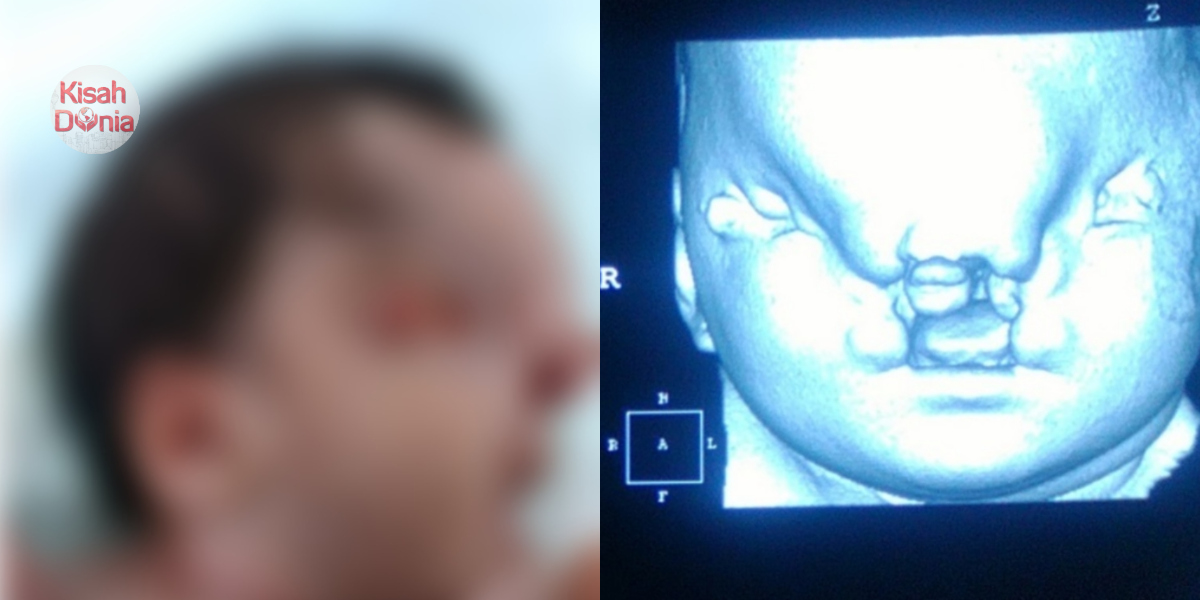

Bayi yang dilahirkan mengalami pelbagai jenis kecacatan di bahagian muka

Pada minggu ke-37 kehamilan, dia akhirnya selamat melahirkan bayi tersebut melalui prosedur caesarean (czer). Namun begitu, bayi itu hanya mempunyai berat sekitar 2.45kg, jauh lebih rendah daripada purata berat bayi baru lahir yang normal. Lebih menyedihkan lagi, si kecil itu turut mengalami Frontonasal Dysplasia iaitu keadaan di mana proses embriogenesis muka mengalami kecacatan.

Akibat daripada itu, matanya disahkan buta, rambut kulit kepala jarang, penonjolan dahi, batang hidung mendap, bibir dan lelangit sumbing yang melibat seluruh kawasan mulut. Posisinya telinga turut berada dalam keadaan terpusing ke belakang selain alat kelamin lebih besar daripada kebiasaan.